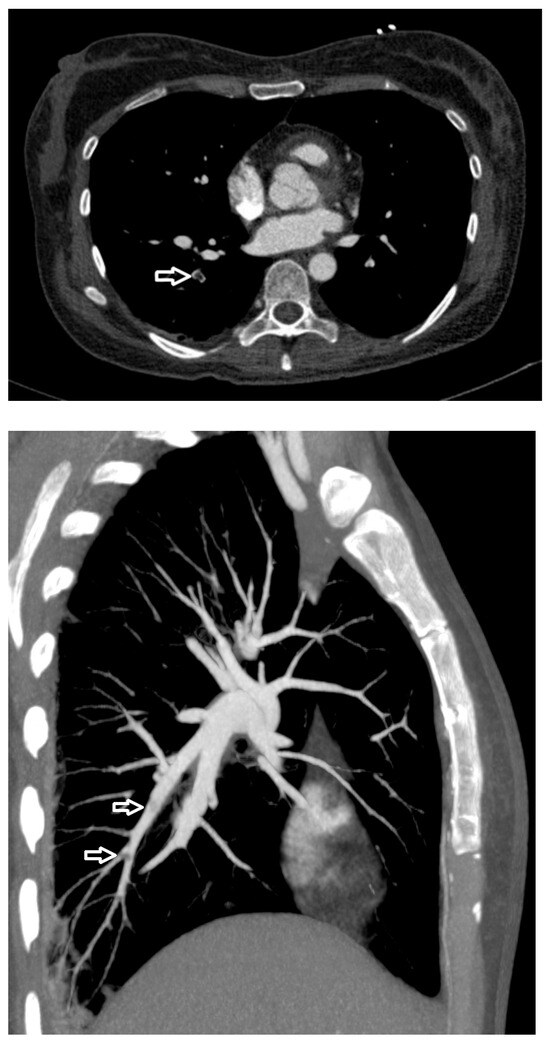

| CTPA | Computed tomography pulmonary angiography |

| PE | Pulmonary embolism |

| PTE | Pulmonary thrombotic embolism |